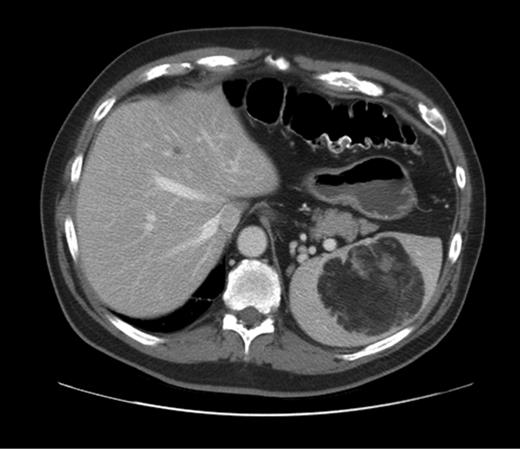

We report a case of a 64-year-old Caucasian man with a past medical history of gout, dyslipidemia, hypertension, obesity, gastroesophageal reflux disease and in previous left hemicolectomy for colon cancer nine years prior to presentation. His past surgical history includes two laparoscopic hernia repairs for incisional hernias after the hemicolectomy. He was referred to the surgery service for new diagnosis of myasthenia gravis and the consideration for possible thymectomy. The thymus was without evidence of thymoma, however, the work-up included radiographic studies demonstrating a centrally located splenic mass measuring 8 × 6.8 cm. The density of the mass was consistent with those found in soft tissue tumors (Fig. 1). A comparison CT study from 9 years previous demonstrated a smaller mass (4.7 cm) in the same anatomic location with similar density levels. There had been no prior treatments. The patient's case was presented at our multi-specialty tumor board and elective resection of the spleen was recommended due to the possibility of malignancy.